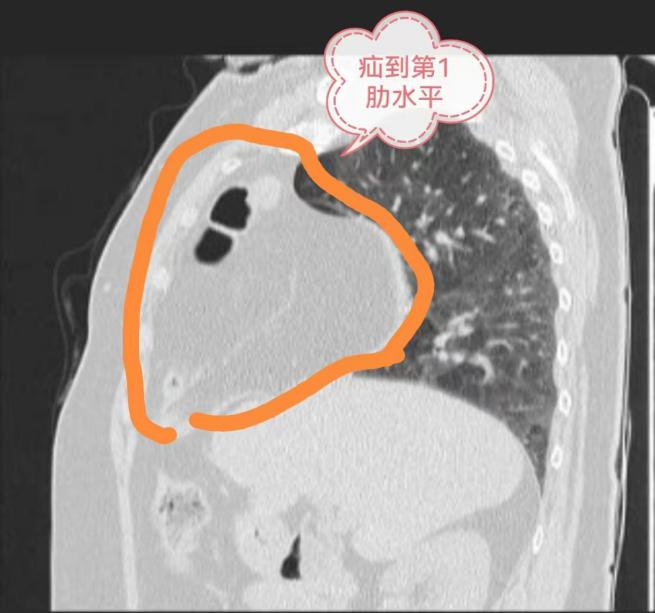

近日,刘奶奶(75岁)来到贵州航天医院做了胸部CT、冠脉造影等检查,经过心血管内科、呼吸与危重症医学科、心胸外科、影像科等多学科会诊讨论,确诊并没有冠心病,而是因为有“膈疝”导致她的一系列症状。而且,刘奶奶的膈疝还非常严重,腹部的肠管和网膜已经“跑”到右侧胸腔顶部去了,还占据了整个右侧前胸腔,难怪会出现那么明显的症状。通常这类严重的膈疝多采用开放手术,需要至少15厘米长的切口。